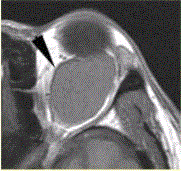

问题 患者女,30岁,左眼球突出,运动障碍7个月。MRI平扫示左肌锥内等T信号影(下图)。增强扫描示均匀增强,眼肌、眼环正常。 诊断应为

选项 A.甲状腺性突眼 B.眼眶疏松结缔组织炎 C.炎性假瘤 D.海绵状血管瘤 E.转移瘤 F.淋巴管瘤

答案 D